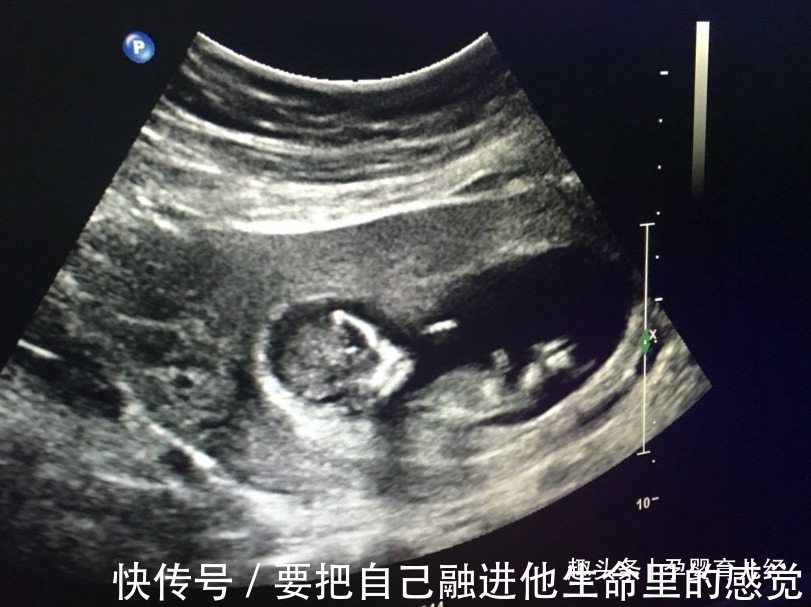

胎儿的性别是从受精卵开始就已经决定了,在孕初期无法看出胎儿的性别,而到了孕十二周,胎儿的性别特征才会一点点显现出来。怀孕十二周,腹中胎儿的不同性别有哪些区别?孕十二周,由于胎儿还处在生长发育阶段,其身长只有约9厘米,重23g左右,相当于3颗草莓的重量。这个阶段我们还只能看到胎心和胎芽,其他器官都还未发育成熟,而胎儿的性别器官已经开始发育,不过都还都未发育完全,因此就算此时通过B超检察胎儿性别,也不一定准确。并且医院有明确规定:不允许通过B超手段,检查胎儿性别,并且不允许医生提前告知胎儿性别,因此就算医生看得出来,也是会“守口如瓶”的。

5、孕16周性别显现比较明显孕十六周胎儿的性别器官才完全发育成熟,这时B超就可以相对准确地看出胎儿的性别了,但也是需要一些运气的,因为有时碰巧遇到胎儿背着身体或四肢遮挡住性别器官,那就没办法确认了。